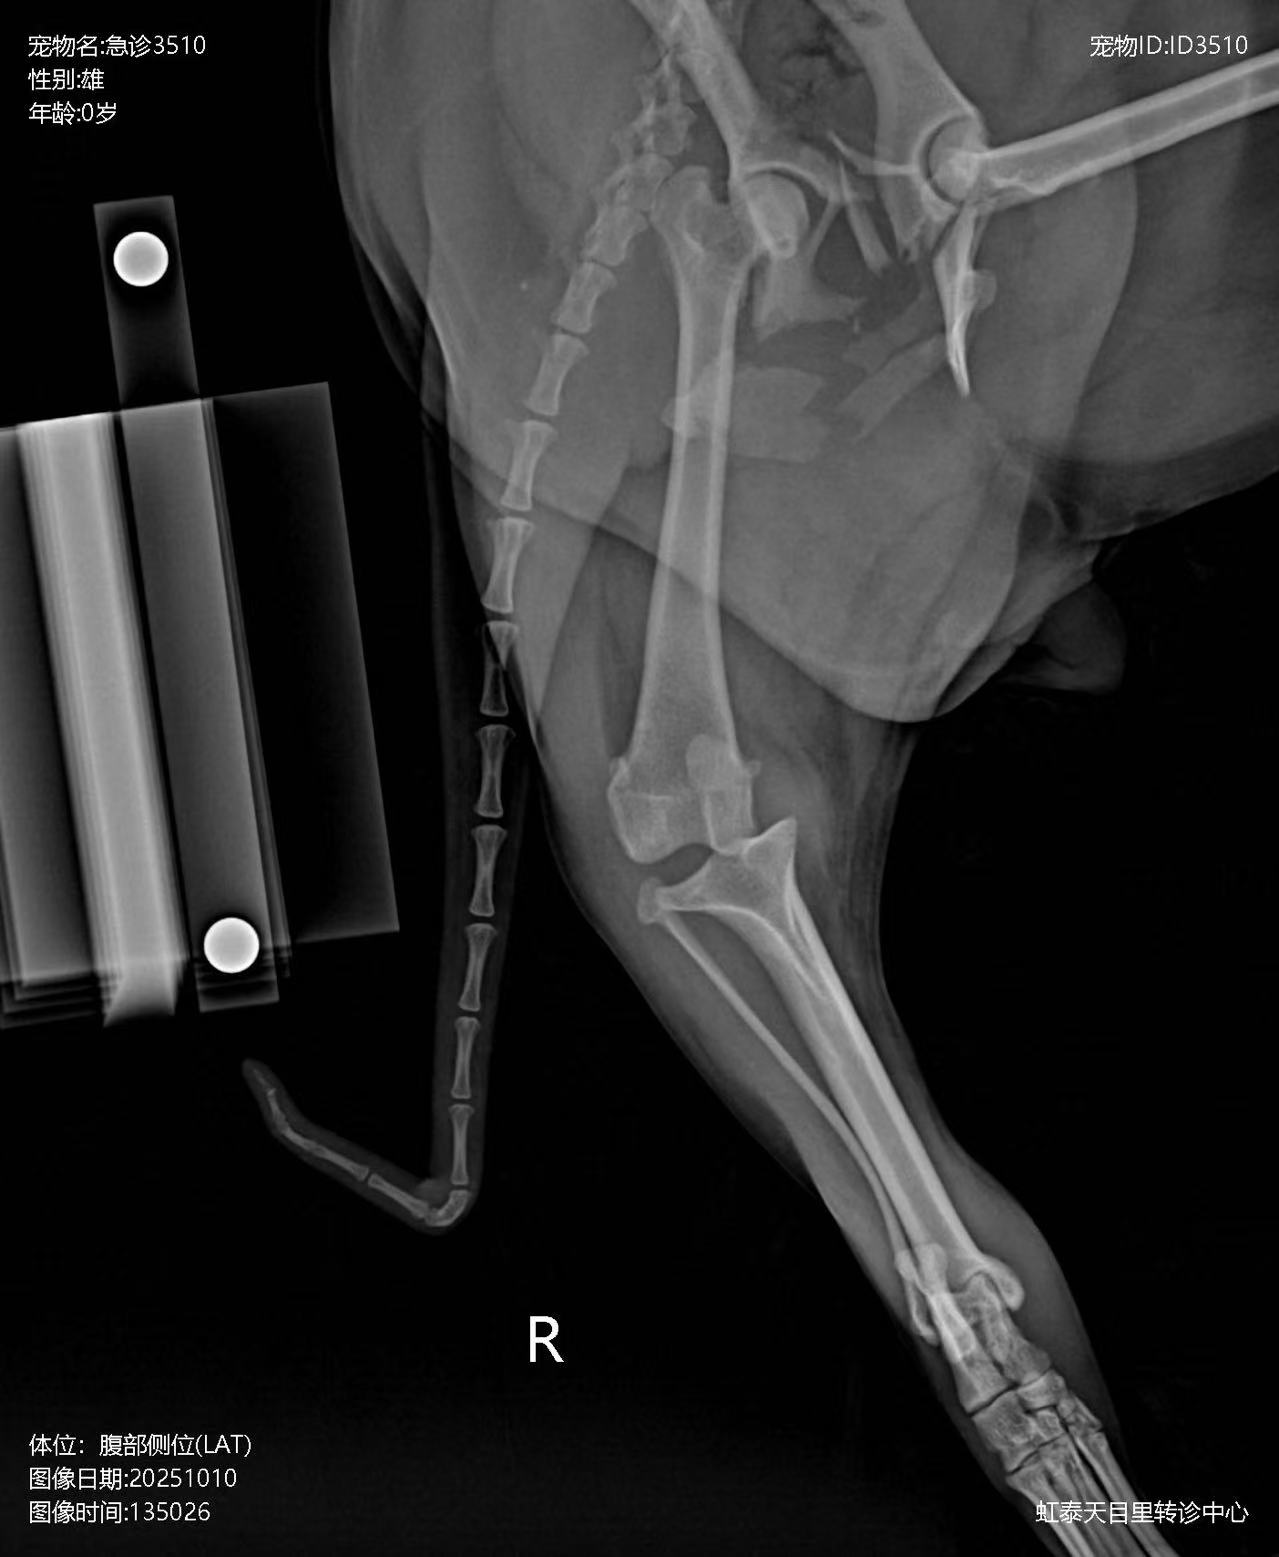

Preoperative X-ray: